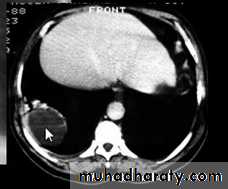

chest practice

Subpulmonary pleural effusion. On the (A) erect PA and (B) lateral radiograph the effusion simulates a high hemidiaphragm. (C) Ultrasound and (D) CT clearly show that the effusion is located above the diaphragm. Arrows = diaphragmatic area.